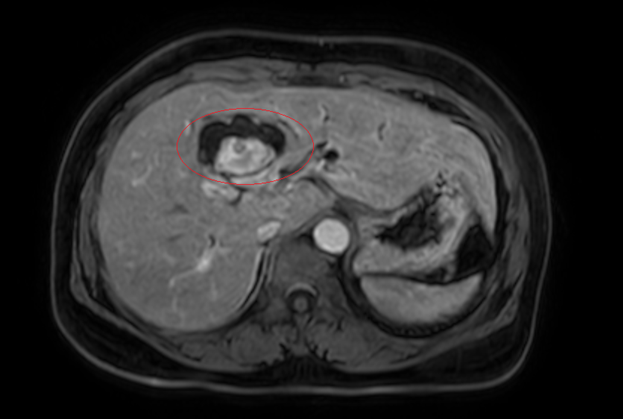

Hình ảnh giãn khu trú đường mật gan trái, tạo cấu trúc dạng nang. Ảnh: Bệnh viện cung cấp

Trước đó, người phụ nữ nhập viện trong tình trạng vàng da, ngứa và đau vùng hạ sườn phải kéo dài. Kết quả chẩn đoán hình ảnh cho thấy tổn thương đường mật trong gan kèm sỏi và giãn đường mật. Trong quá trình thăm khám toàn diện, nội soi tiêu hóa phát hiện thêm một khối u tại đại tràng lên. Kết quả sinh thiết xác định đây là ung thư biểu mô tuyến.

Sau hội chẩn đa chuyên khoa, các bác sĩ xác định bệnh nhân mắc đồng thời hai ung thư nguyên phát, thay vì một khối u di căn. Cụ thể, ung thư đại tràng phải giai đoạn sớm, chưa di căn hạch và ung thư đường mật trong gan giai đoạn tiến triển, có xâm lấn và di căn hạch.